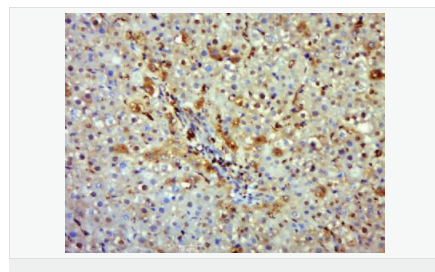

| 產品應用 | WB=1:500-2000 IHC-P=1:100-500 IHC-F=1:100-500 Flow-Cyt=1μg/Test ICC=1:100-500 IF=1:100-500 (石蠟切片需做抗原修復) not yet tested in other applications. optimal dilutions/concentrations should be determined by the end user. |

| 產品介紹 | Nitric oxide (NO) is an inorganic, gaseous free radical that carries a variety of messages between cells. Vasorelaxation, neurotransmission and cytotoxicity can all be potentiated through cellular response to NO. NO production is mediated by members of the nitric oxide synthase (NOS) family. NOS catalyzes the oxidization of L-arginine to produce L-citrulline and NO. Two constitutive isoforms, brain or neuronal NOS (b or nNOS, type I) & endothelial cell NOS (eNOS, type III), and one inducible isoform (iNOS, type II), have been cloned. All NOS isoforms contain calmodulin, nicotinamide adenine dinucleotide phosphate (NADPH), flavin adenine dinucleotide (FAD), and flavin mononucleotide (FMN) binding domains. Nitric oxide synthase is expressed in liver, macrophages, hepatocytes, synoviocytes, stimulated glial cells and smooth muscle cells. Cytokines such as interferon-gamma (IFN), tumor necrosis factor (TNF), interleukin-1 and -2, and lipopolysaccarides (LPS) cause an increase in iNOS mRNA, protein, and activity levels. Protein kinase C-stimulating agents exhibit the same effect on iNOS activity. After cytokine induction, iNOS exhibits a delayed activity response which is then followed by a significant increase in NO production over a long period of time. Human iNOS is regulated by calcium/calmodulin (in contrast with mouse NOS2). Function: Produces nitric oxide (NO) which is a messenger molecule with diverse functions throughout the body. In macrophages, NO mediates tumoricidal and bactericidal actions. Also has nitrosylase activity and mediates cysteine S-nitrosylation of cytoplasmic target proteins such COX2. Subunit: Homodimer. Binds SLC9A3R1. Tissue Specificity: Expressed in the liver, retina, bone cells and airway epithelial cells of the lung. Not expressed in the platelets. Similarity: Belongs to the NOS family. Contains 1 FAD-binding FR-type domain. Contains 1 flavodoxin-like domain. SWISS: P35228 Gene ID: 4843 Database links: Entrez Gene: 4843 Human Entrez Gene: 18126 Mouse Omim: 163730 Human SwissProt: P35228 Human SwissProt: P29477 Mouse Unigene: 709191 Human Unigene: 2893 Mouse Unigene: 10400 Rat Important Note: This product as supplied is intended for research use only, not for use in human, therapeutic or diagnostic applications. 合成與降解(Synthesis and Degradation) 催化生物體內一氧化氮(NO)生成的酶。分神經(jīng)型一氧化氮合成的酶(nNOS or NOS-1)、誘導型一氧化氮合成的酶(iNOS or NOS-2)、內皮型一氧化氮合成的酶(eNOS or NOS-3)。 |